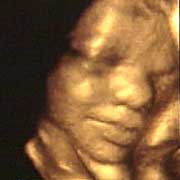

圖文:胎兒子宮內(nèi)表情豐富 專家稱提供研究新依據(jù)

中新網(wǎng)9月13日電 英國天空新聞報道,英國科學家圖亞特·坎貝爾最近利用先進的掃描技術(shù)清晰地拍下了孕婦子宮中胎兒的表情,透過他拍攝的照片,人們可以清楚的看到一個尚未降臨世間的小生命喜、怒、哀、樂的表情。

斯圖亞特.坎貝爾是倫敦著名的產(chǎn)科教授,他利用超聲掃描技術(shù)拍攝到了胎兒在子宮中打呵欠、眨眼、吮手指、哭泣甚至微笑的畫面,這些都為胎兒行為的研究提供了新的依據(jù),專家認為,這一突破將推動嬰兒健康科學的發(fā)展,包括對唐氏綜合癥等嬰幼兒疾病的診治將起到極大的推動作用。